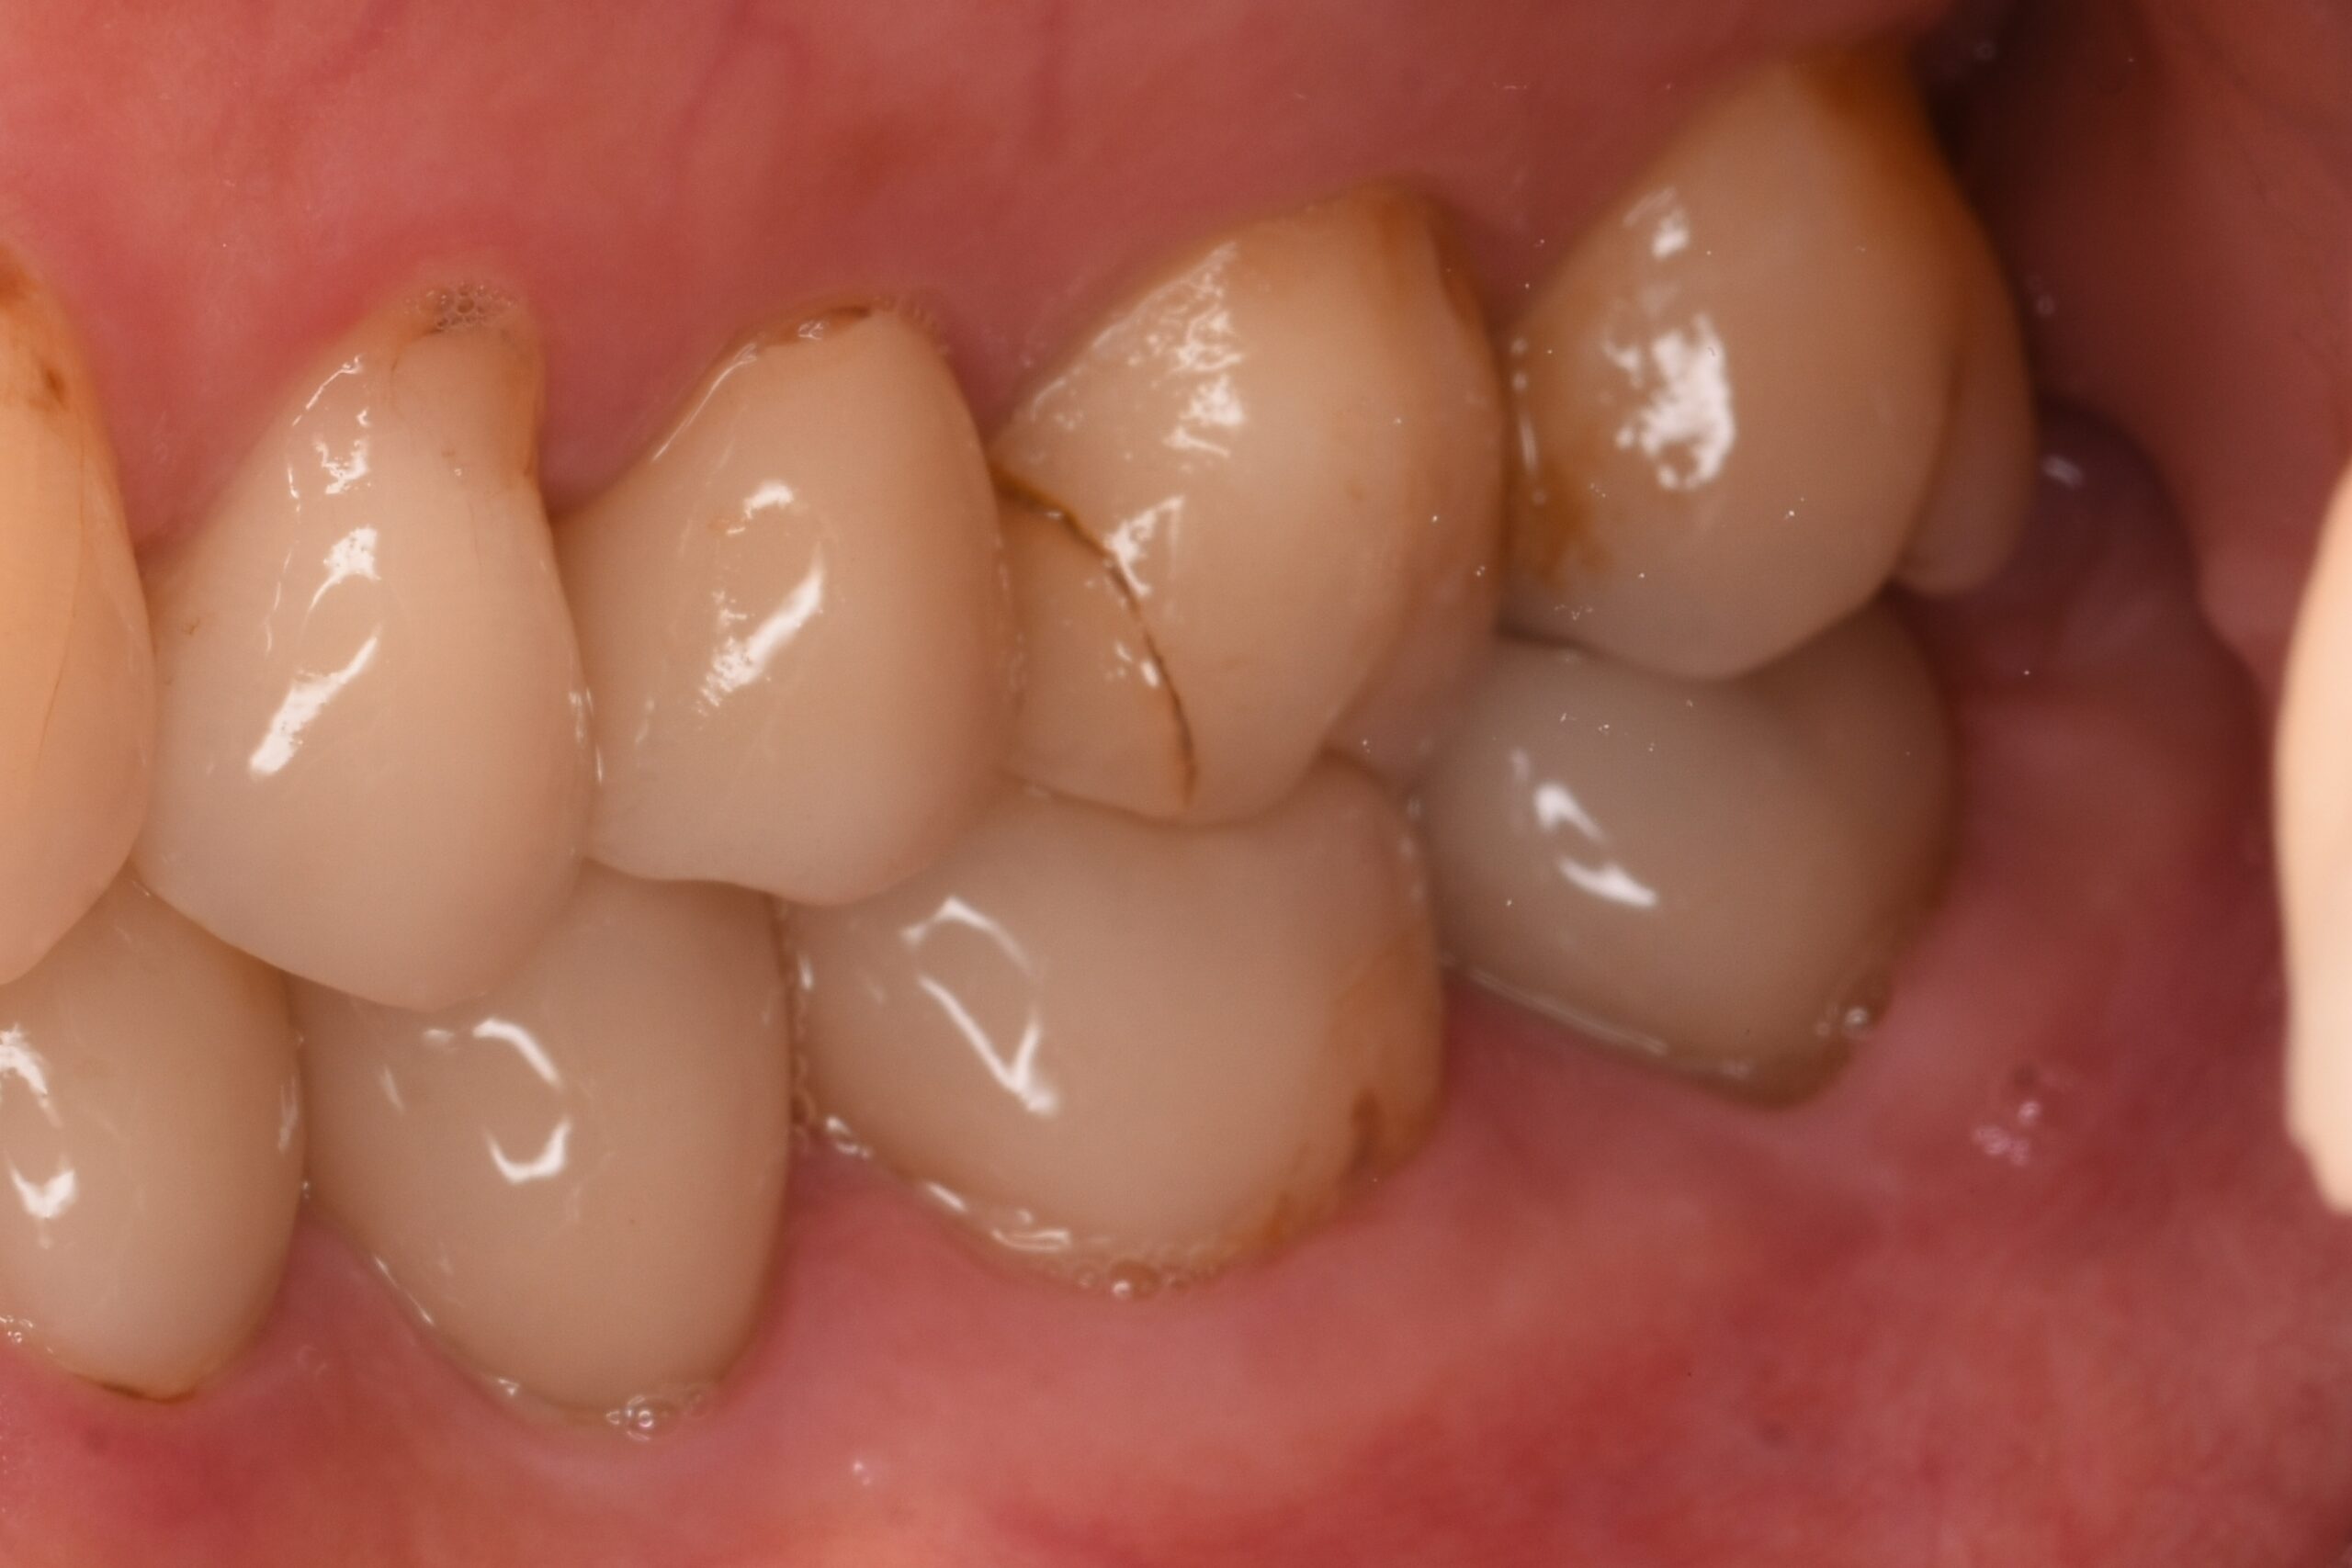

• after

根管内が清潔になったことを確認した後、薬剤を充填し、最終的に被せ物などで歯を補強します。

左下5番 根幹治療・e.maxクラウン 左上6番 e.maxクラウン 左上7番 根管治療・e.maxクラウン